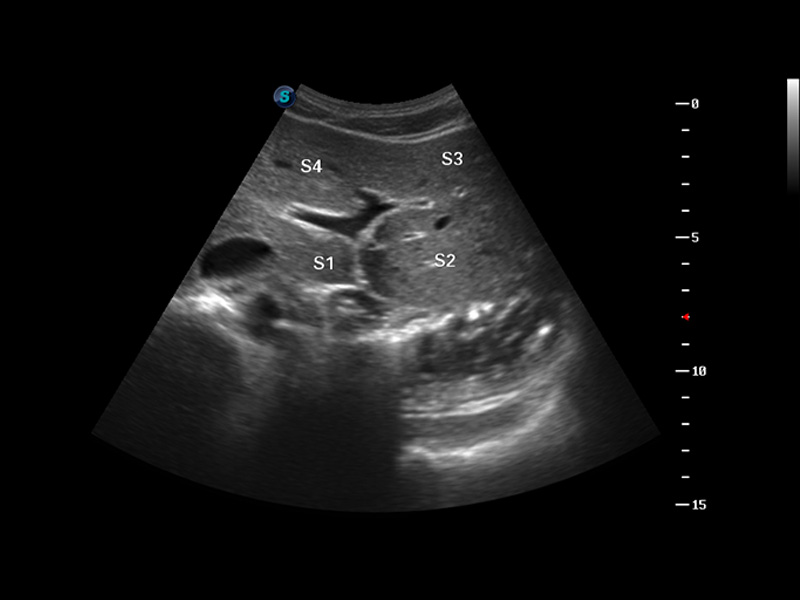

谐波成像

3D/4D成像